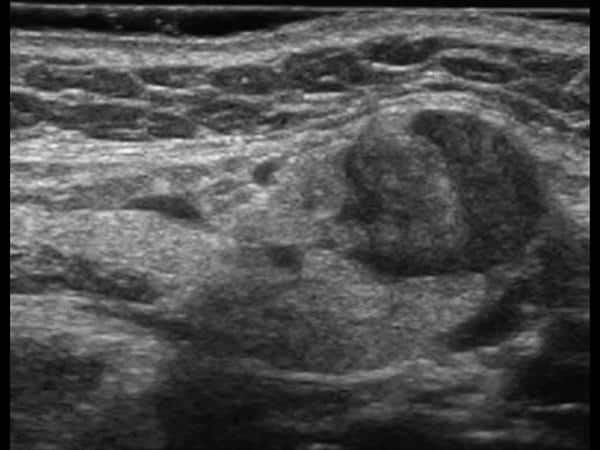

U tuyến nước bọt

» Thông tin: Nữ giới – 60 tuổi.

» Lâm sàng: Khối vùng góc hàm.

# Di căn tuyến nước bọt dưới hàm.